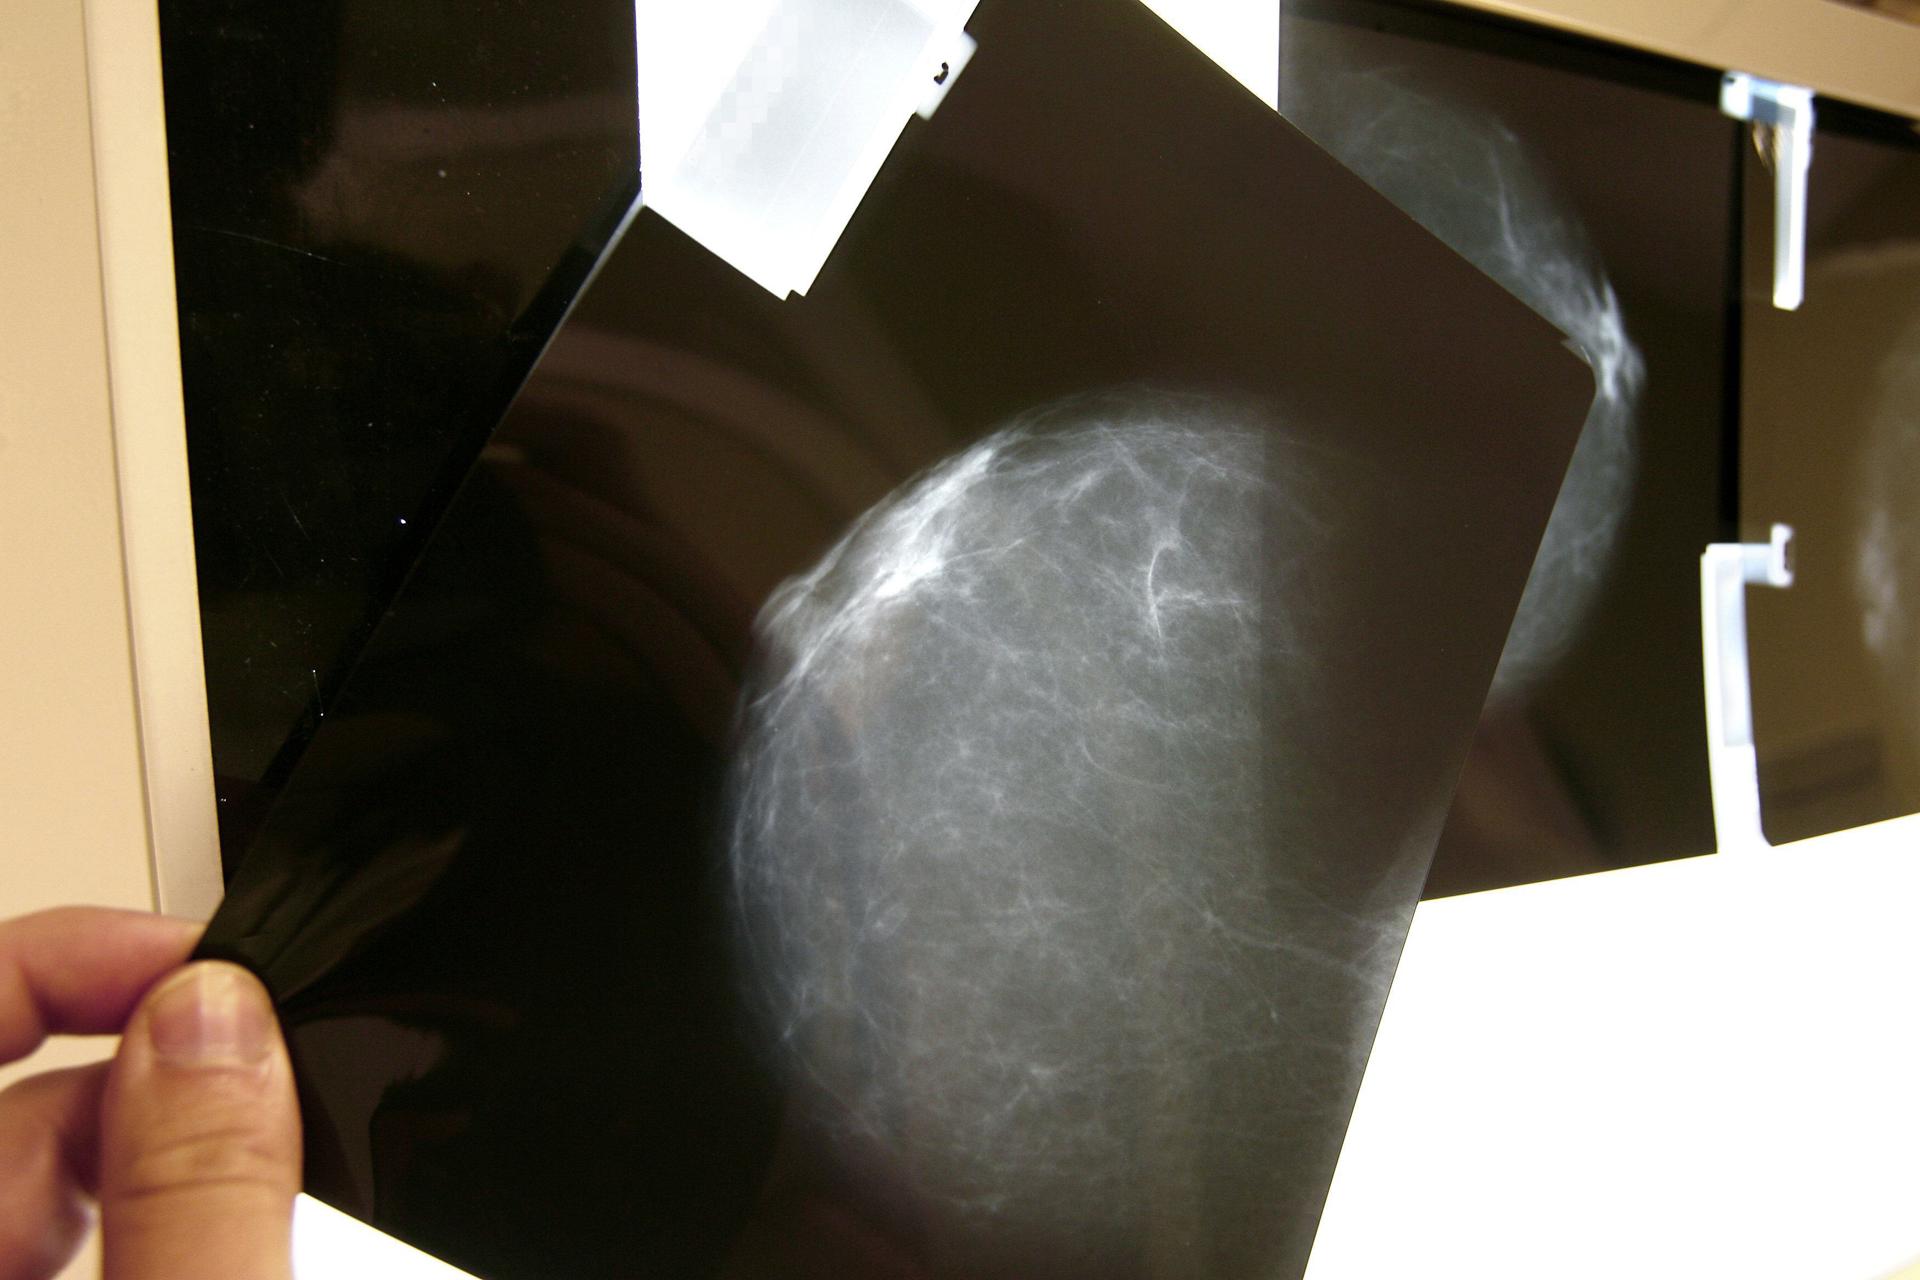

Un estudio del Instituto de Salud Carlos III de España, basado en el análisis de 714 pacientes con cáncer de mama, sugiere que tener mayor densidad mamográfica podría estar relacionado con el desarrollo de algunos tumores, como los HER2+ o los triple negativo, que son los más agresivos y con peor pronóstico.

La densidad mamográfica mide la proporción de tejido fibroglandular de una mama, frente a la cantidad de tejido graso. Cuanto más densas, más tejido fibroso tienen y mayor es el riesgo de cáncer de mama.

El estudio ha analizado la relación entre densidad mamográfica y los subtipos de cáncer de mama y también la posible influencia del índice de masa corporal y el estado menopáusico, explica el ISCIII en un comunicado.

El 69% de las participantes presentó tumores HR+, un 19% el subtipo HER2+ y un 12% el triple negativo, y la densidad mamográfica media fue del 26%.

Las mujeres con densidad mamográfica superior al 50% presentaron un menor porcentaje de tumores con mejor pronóstico (HR+), mientras que el porcentaje de tumores HER2+ y triple negativo -los más agresivos- fue un 36% y un 23% mayor, respectivamente, en comparación con las mujeres del grupo de menor densidad.